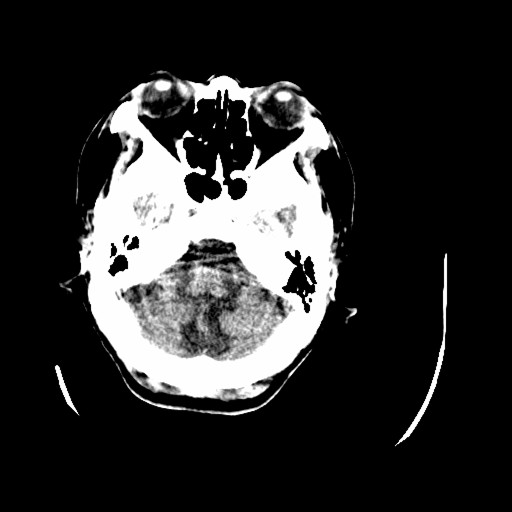

标题: CT16233:女,44岁,智障多年,现感头痛 [打印本页]

标题: CT16233:女,44岁,智障多年,现感头痛

小脑有啥病变?

橄榄桥小脑萎缩.左侧小脑脚腔梗.

为什么不考虑发育畸形呢

1)小脑萎缩。2)小脑蚓部发育不良。

橄榄桥小脑萎缩可能,建议mri进一步检查以进一步排查。

小脑萎缩征,原因待定.

橄榄桥小脑萎缩